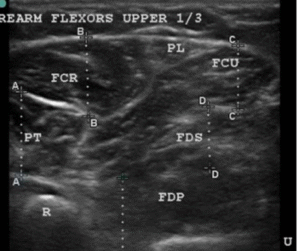

Most of our papers got rejected outright and there was not much we could do about it without some kind of objective evidence that could prove our hypotheses. This opportunity came in 2009. An ultrasonography (USG) machine company brought their machine for demonstration. So, I thought ‘let us see if the intrinsic muscle issues of CRPS can be visualized on USG’. I had two patients of CRPS in the clinic that day and what I saw on USG just blew me away. USG unequivocally showed in black and white what I had suspected all the time, that there was an intrinsic muscle abnormality in CRPS. This was obvious even to me without a formal training in muscle sonoanatomy.

Normal muscle on USG has clearly delineated muscle outlines and looks generally black with bright streaks of connective tissue framework that holds the muscle fibers in well-defined bundles. (fig 15) In stark contrast, the CRPS muscles in this patient looked like a sheet of barren white (fibrotic) tissue without any form or shape, with no discernible outlines. The bulk of muscle was also very much reduced in CRPS compared to normal muscles.

Row 1- The ultrasound appearance of a normal muscle from the healthy limb. Note that the outlines of the muscles are clearly defined by shiny white borders and all the different muscles are identifiable and can be named. The muscles themselves have a dark background within a framework of supporting fibrous tissue which appears like shiny white streaks, and this is the typical sonographic signature of muscle. The second image shows her hand trying to make a fist, that she is unable to flex the fingers onto the palm or touch the tips of fingers to each other or thumb. Ultrasound of the CRPS limb in the 3rd image shows that there is no definition of muscle boundaries nor is there the normal contrast of black muscle in with white streaks of fibrous framework in between as compared to the ultrasound of the muscles of normal limb. In short there is a complete disruption of muscle structure.

2nd row- The first image shows that the patient has regained the ability to make a fist after 1month of USGDN of the forearm muscles. The patient opening the cap of a bottle 18 days after treatment which was impossible for her before USGDN at Ashirvad. Image C shows the return of normal structure to the muscles on ultrasound although there is still some predominance of fibrosis in the form of hyperechogenic fibrous streaks.

We found that these ultrasound changes of muscle structure disruption were consistently present in varying degrees in every patient that we examined thereafter. The USG changes of muscle abnormality appear as early as 15 days after the onset of CRPS and continue to be not just present but keep worsening till the muscle becomes completely fibrotic as indicated by the white-out appearance in all muscles affected by CRPS of medium or long duration. This was the picture that we saw in the first patient who had CRPS for 2 years. Subsequently we made it a part of our CRPS management protocol to routinely to document the muscle changes in every patient before USGDN, at 15 and 30 days and after the patient has recovered fully and correlate it with documentation of clinical findings.

How and why this muscle changes occurred was still a mystery, but the documentation went on both of USG, and the variety of clinical presentations. This systematic documentation was crucial to the acceptance of our findings by the scientific community and for us to publish our unusual findings in CRPS with a safe and effective treatment like USGDN in reputed international journals. Our first article “Ultrasound Appearance of Forearm Muscles in Eighteen Patients with Complex Regional Pain Syndrome Type -1 of the Upper Extremity” was provisionally accepted in 2011 but was finally published in 2012 and the printed version came out in January 2013 edition of the journal Pain Practice. (51)